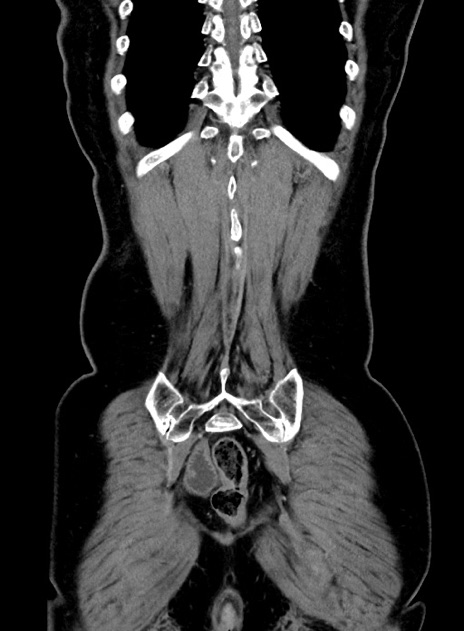

症例9(冠状断像)

【症例】 60歳代女性

【主訴】むかつき、みぞおちの痛み

【現病歴】3日前よりむかつきがあり、食事がとれない。

【既往歴】糖尿病

【身体所見】発熱なし、心窩部圧痛軽度あるも、腹膜刺激症状なし。

【データ】WBC 7400、CRP 1.92